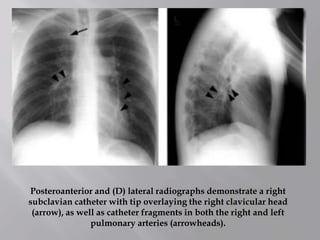

Posteroanterior and (D) lateral radiographs demonstrate a right

subclavian catheter with tip overlaying the right clavicular head

(arrow), as well as catheter fragments in both the right and left

pulmonary arteries (arrowheads).